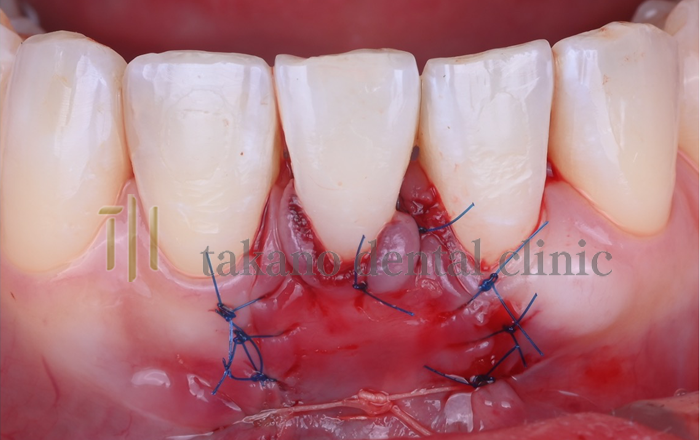

下がった歯ぐきを治療するためには歯周形成外科治療が必要になります下がった歯ぐきを治療するためには歯周形成外科治療が必要になります。外科治療には遊離歯肉移植術、結合組織移植術、歯肉弁歯冠側移動術といった手術をおこないます。

結合組織移植術

case01

• 術前

治療例

• 術中

• 術後